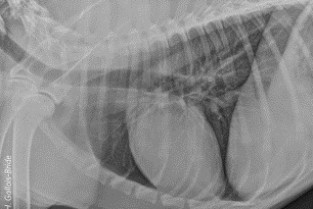

Le GEIM vous propose une séance de travaux pratiques de radiographies sur le thorax. Tous les aspects sont abordés sous la forme de TP de lecture de radiographies numériques sur station de travail Osirix sur Mac (3 vétérinaires maximum/ordinateur).

- décrire les principes à respecter pour obtenir une radiographie thoraciques de bonne qualité ;

- adopter une méthodologie pour interpréter les affections de la cage thoracique, de la plèvre, du médiastin et des poumons chez les carnivores domestiques ;

- connaître l’aspect normal et anormal de la cage thoracique, de la plèvre, du médiastin et des poumons chez les carnivores domestiques.